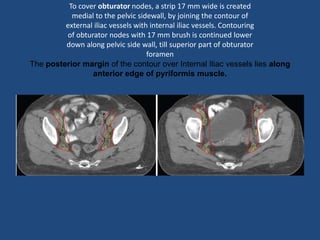

To cover obturator nodes, a strip 17 mm wide is created

medial to the pelvic sidewall, by joining the contour of

external iliac vessels with internal iliac vessels. Contouring

of obturator nodes with 17 mm brush is continued lower

down along pelvic side wall, till superior part of obturator

foramen

The posterior margin of the contour over Internal Iliac vessels lies along

anterior edge of pyriformis muscle.